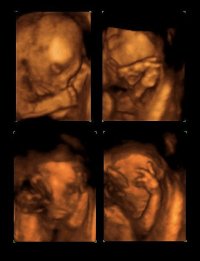

Mh sonst habe ich erst in 4 Wochen einen rundumschlag CTG Ultraschall und Doppler dazu sagte er das der muttermund die durchblutung getestet wird oh ich freu mich schon. Habe gestern ja kein Ultraschall bekommen jedoch davor 3D machen lassen also hab ich ja den kleinen gesehen. Und die wochen gehen sowieso soooo schnell um zum Glück.

• baby.jpg

baby.jpg

@ stefanie schön das es deinen kleine gut geht, tolle Fotos :inlove